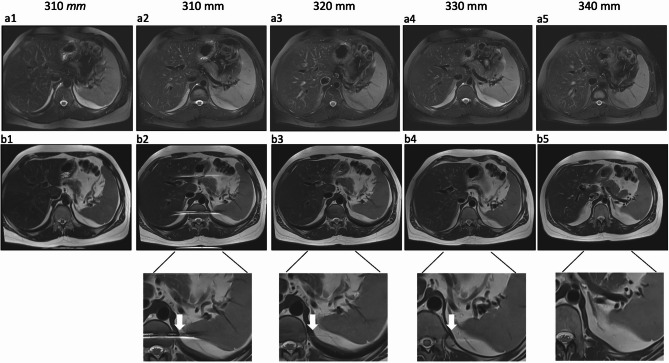

Materials and methods: DL-HASTE of the upper abdomen was acquired with variable sequence parameters regarding FS, flip angle (FA) and field of view (FOV) in 10 healthy volunteers and 50 patients. DL-HASTE sequences were compared to clinical sequences (HASTE, HASTE-FS and T2-TSE-FS BLADE). Two radiologists independently assessed the sequences regarding scores of overall image quality, delineation of abdominal organs, artifacts and fat saturation using a Likert scale (range: 1-5).

Results: Breath-hold time of DL-HASTE and DL-HASTE-FS was 21 ± 2 s with fixed FA and 20 ± 2 s with variable FA (p < 0.001), with no overall image quality difference (p > 0.05). DL-HASTE required a 10% larger FOV than DL-HASTE-FS to avoid aliasing artifacts from subcutaneous fat. Both DL-HASTE and DL-HASTE-FS had significantly higher overall image quality scores than standard HASTE acquisitions (DL-HASTE vs. HASTE: 4.8 ± 0.40 vs. 4.1 ± 0.50; DL-HASTE-FS vs. HASTE-FS: 4.6 ± 0.50 vs. 3.6 ± 0.60; p < 0.001). Compared to the T2-TSE-FS BLADE, DL-HASTE-FS provided higher overall image quality (4.6 ± 0.50 vs. 4.3 ± 0.63, p = 0.011). DL-HASTE achieved significant higher image quality (p = 0.006) and higher sharpness score of organs compared to DL-HASTE-FS (p < 0.001).